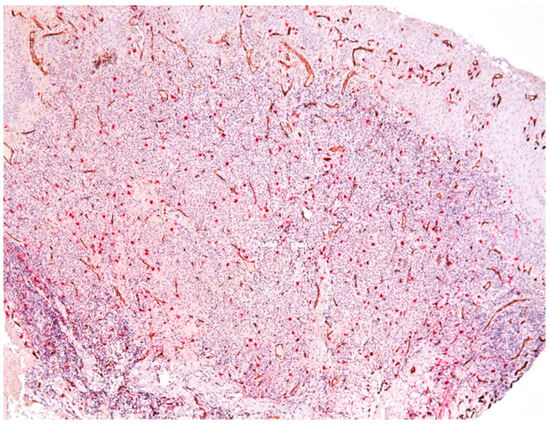

3.2. Mast Cells

3.3. Aspects of Microvessels

3.4. MCD and MVD

| Intraepithelial Mast Cells | Subepithelial Mast Cells | Connective Tissue Mast Cells |

|---|---|---|

| Mean (SD): 2.1 (1.9) | Mean (SD): 6.5 (4.8) | Mean (SD): 18.7 (7.7) |

| Range: 0.0–7.3 | Range: 0.0–13.7 | Range: 6.3–34.3 |

| Intraepithelial Vessels | Subepithelial Vessels | Connective Tissue Vessels |

| Mean (SD): 1.4 (2.2) | Mean (SD): 7.8 (6.5) | Mean (SD): 14.9 (3.9) |

| Range: 0.0–9.7 | Range: 0.0–20.3 | Range: 0.0–23.2 |